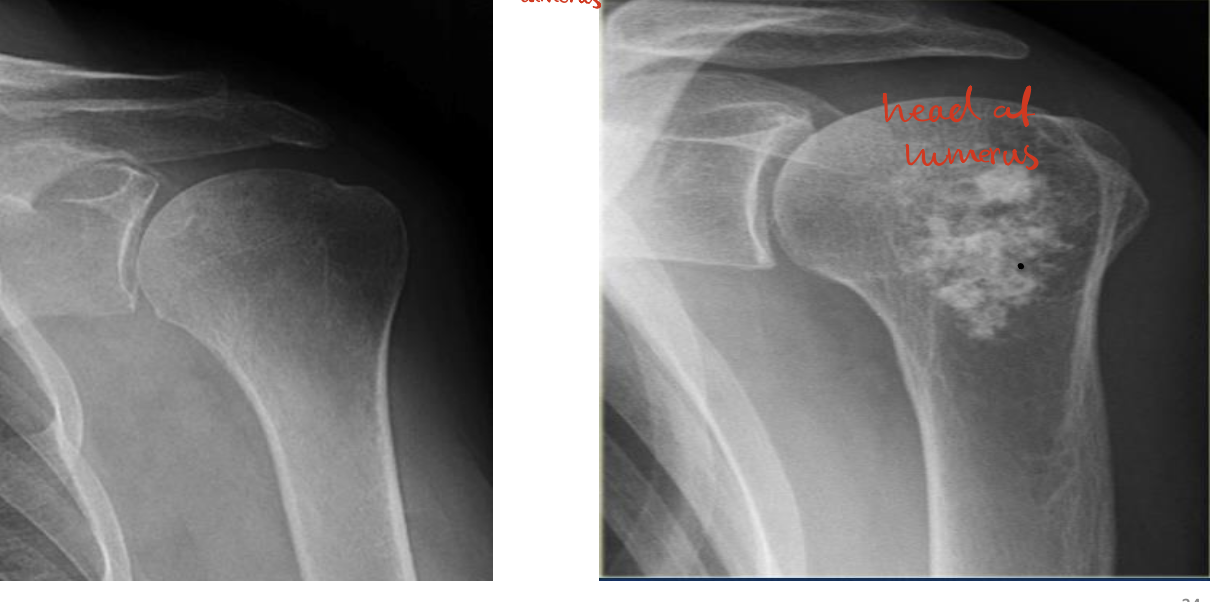

Identify 4 joints ? What view? WHAT IS THAT ?

Sholder Joint

AcromioClavicular Joint

ThoracoScapular Joint

SternoClavicular Joint

— Antero-Posterior View

— X-ray of shoulder

Identify the structures ? name of the bone ?

— Humerus

• 1, Clavicle.

• 2, Acromion.

• 3, Greater tubercle.

• 4, Lesser tubercle.

• 5, Neck of the humerus

• 6, Humerus.

• 7, Coracoid Process.

• 8, Scapula

• 9, Rib.

• Arrow, Glenohumeral joint space.